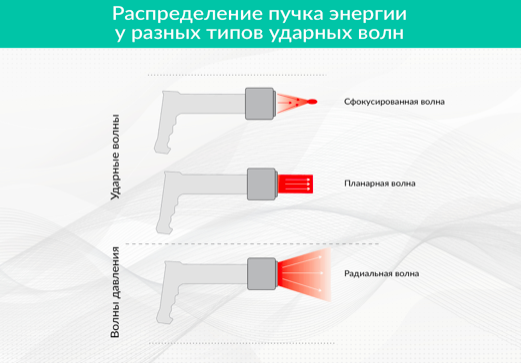

В современной теории ударно-волновой терапии условно принято выделять три типа ударной волны (ниже см. рисунок 1):

- фокусированную;

- планарную;

- радиальную.

Планарная и фокусированная волны относятся к «классическим» ударным волнам, как это понимается в акустике. Они генерируются с помощью:

Радиальные ударные волны имеют отношение к так называемым расфокусированным волнам давления, расходясь из источника широким потоком во все стороны, и чем-то напоминая воду льющуюся из душа и не имеют фокусного пятна, где концентрируется энергия.

Каждый из трех типов распределения волны имеет свои характеристики волнового фронта и профиля распределения энергии, во многом обусловленные конструкциями и видами преобразователей соответствующих аппаратов УВТ. Они представляют собой волны давления или ударные волны со специфическим набором диапазонов количественных характеристик крутизны фронтов, давлений, профилей распределения энергий. Эти характеристики очень важны в терапевтическом плане и вызывают различные типы биологических и прочих эффектов при воздействии на живую ткань организма.

Рисунок 1. Типы ударных волн